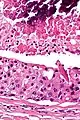

Low magnification micrograph of a salivary duct carcinoma with characteristic comedonecrosis (left of image) adjacent to normal parotid gland (right of image). H&E stain.

Their histologic appearance is similar to ductal breast carcinoma.